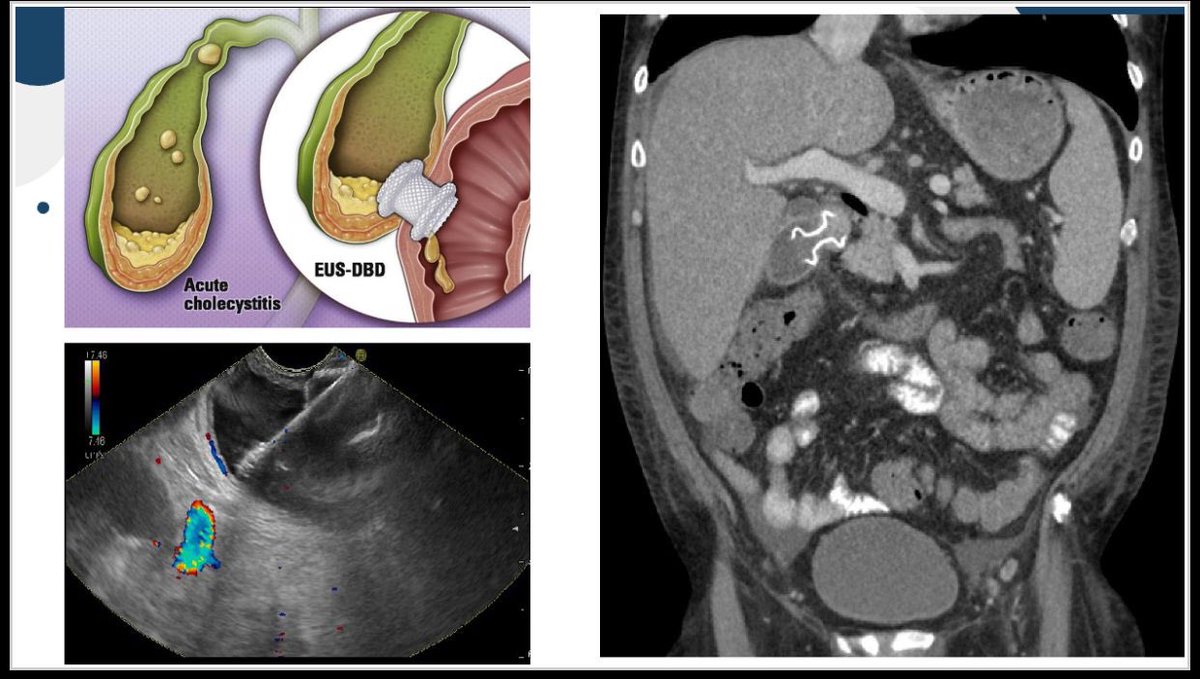

تسخدم في علاج المرارة في حالة تعذر العمليات وكحل افضل بدل ثقب المرارة خارجيا